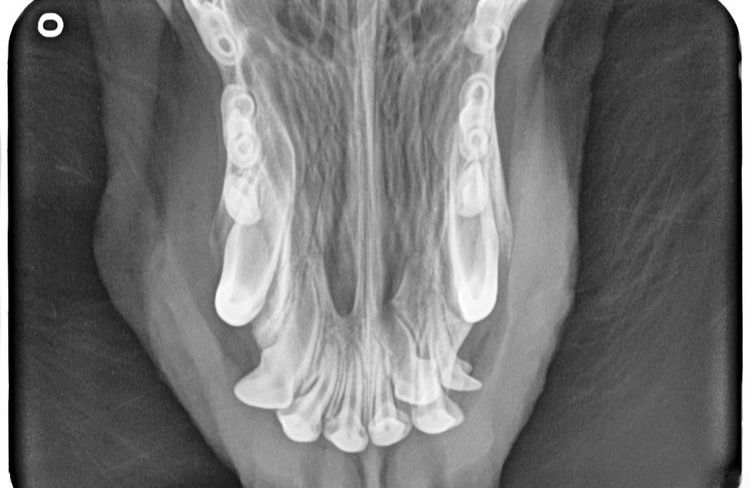

Tout d'abord, un examen approfondi est réalisé, au cours duquel le vétérinaire évalue l'état et la symétrie du museau. Ensuite, un examen buccal est effectué afin de déterminer l'étendue et la nature de la blessure.

Si le processus pathologique touche les tissus profonds, une radiographie de la mâchoire supérieure ou inférieure est nécessaire. Une sédation est souvent utilisée pour garantir un examen radiologique serein. Le vétérinaire détermine la position optimale de la tête de l'animal afin d'obtenir une radiographie de haute qualité et informative. Dans la plupart des cas, la radiographie est réalisée mâchoire ouverte.